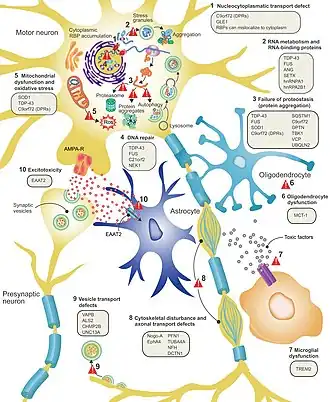

Biochemistry

It is still not fully understood why neurons die in ALS, but this neurodegeneration is thought to involve many different cellular and molecular processes.[9] The genes known to be involved in ALS can be grouped into three general categories based on their normal function: protein degradation, the cytoskeleton, and RNA processing.[85] Mutant SOD1 protein forms intracellular aggregations that inhibit protein degradation. Cytoplasmic aggregations of wild-type (normal) SOD1 protein are common in sporadic ALS.[80] It is thought that misfolded mutant SOD1 can cause misfolding and aggregation of wild-type SOD1 in neighboring neurons in a prion-like manner.[10] Other protein degradation genes that can cause ALS when mutated include VCP, OPTN, TBK1, and SQSTM1. Three genes implicated in ALS that are important for maintaining the cytoskeleton[80] and for axonal transport[10] include DCTN1, PFN1, and TUBA4A.[80]

Several ALS genes encode RNA-binding proteins. The first to be discovered was TDP-43 protein,[80] a nuclear protein that aggregates in the cytoplasm of motor neurons in almost all cases of ALS; however, mutations in TARDBP, the gene that codes for TDP-43, are a rare cause of ALS.[10] FUS codes for FUS, another RNA-binding protein with a similar function to TDP-43, which can cause ALS when mutated.[61] It is thought that mutations in TARDBP and FUS increase the binding affinity of the low-complexity domain, causing their respective proteins to aggregate in the cytoplasm.[86] Once these mutant RNA-binding proteins are misfolded and aggregated, they may be able to misfold normal proteins both within and between cells in a prion-like manner.[80] This also leads to decreased levels of RNA-binding protein in the nucleus, which may mean that their target RNA transcripts do not undergo normal processing.[87] Other RNA metabolism genes associated with ALS include ANG, SETX, and MATR3.[10]

C9orf72 is the most commonly mutated gene in ALS and causes motor neuron death through a number of mechanisms.[80] The pathogenic mutation is a hexanucleotide repeat expansion (a series of six nucleotides repeated over and over);[88] people with up to 30 repeats are considered normal, while people with hundreds or thousands of repeats can have familial ALS, frontotemporal dementia, or sometimes sporadic ALS.[89] The three mechanisms of disease associated with these C9orf72 repeats are deposition of RNA transcripts in the nucleus, translation of the RNA into toxic dipeptide repeat proteins in the cytoplasm, and decreased levels of the normal C9orf72 protein.[80] Mitochondrial bioenergetic dysfunction leading to dysfunctional motor neuron axonal homeostasis (reduced axonal length and fast axonal transport of mitochondrial cargo) has been shown to occur in C9orf72-ALS using human induced pluripotent stem cell (iPSC) technologies coupled with CRISPR/Cas9 gene-editing, and human post-mortem spinal cord tissue examination.[90]

Excitotoxicity, or nerve cell death caused by high levels of intracellular calcium due to excessive stimulation by the excitatory neurotransmitter glutamate, is a mechanism thought to be common to all forms of ALS. Motor neurons are more sensitive to excitotoxicity than other types of neurons because they have a lower calcium-buffering capacity and a type of glutamate receptor (the AMPA receptor) that is more permeable to calcium. In ALS, there are decreased levels of excitatory amino acid transporter 2 (EAAT2), which is the main transporter that removes glutamate from the synapse; this leads to increased synaptic glutamate levels and excitotoxicity. Riluzole, a drug that modestly prolongs survival in ALS, inhibits glutamate release from presynaptic neurons; however, it is unclear if this mechanism is responsible for its therapeutic effect.[10]